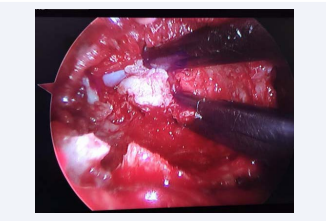

Figure 2 Microendoscopic view of lumbar discectomy for prolapsed  intervertebral disc.

Figure 2 Microendoscopic view of lumbar discectomy for prolapsed intervertebral disc

Prolapsed intervertebral disc (PID) and spinal stenosis with or without associated instability are the commonest indication for surgical intervention in the lumbar spine. MISS techniques can be applied using tubular retractors and assisted by microscope or endoscope to decompress the spinal canal and perform discectomy. The surgical approach can be via the more traditional posterior route, or a transforaminal approach using a percutaneous endoscope. The learning curve for these procedures is variable and maybe associated with higher complication rates, particularly with low-volume practices [14]. MISS decreases surgical trauma and postoperative pain, which leads to improved recovery and decreased hospital length of stay, although there is still a paucity of high quality evidence to support this, and its cost-effectiveness is still undetermined [15] (Figure 2).